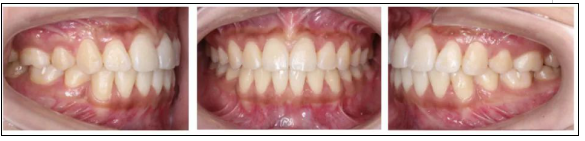

2.* 口內(nèi)檢查(以及調(diào)節(jié)前后口內(nèi)對比):

* 口內(nèi)檢查(以及調(diào)節(jié)前后口內(nèi)對比):

矯正前

口腔衛(wèi)生稍差,軟垢色素(+),牙齦略充血、腫大;恒牙列;左側(cè)磨牙遠(yuǎn)中關(guān)系,右側(cè)磨牙中性關(guān)系;前牙開牙合、深覆牙合;上下牙弓尖圓型;上下牙列輕度擁擠;上中線基本正,下中線左偏。

矯正后

上下牙列齊,前牙覆牙合覆蓋正常,中線正,雙側(cè)尖牙及磨牙關(guān)系中性,雙側(cè)后牙尖窩關(guān)系良好。

* 模型分析(以及調(diào)節(jié)前后模型對比):

上牙列擁擠2.5 mm,下牙列擁擠1 mm;前牙開牙合2 mm,覆蓋4 mm;下中線左偏1.5 mm;Spee曲線深1.5 mm;前牙及全牙Bolton比基本正常。